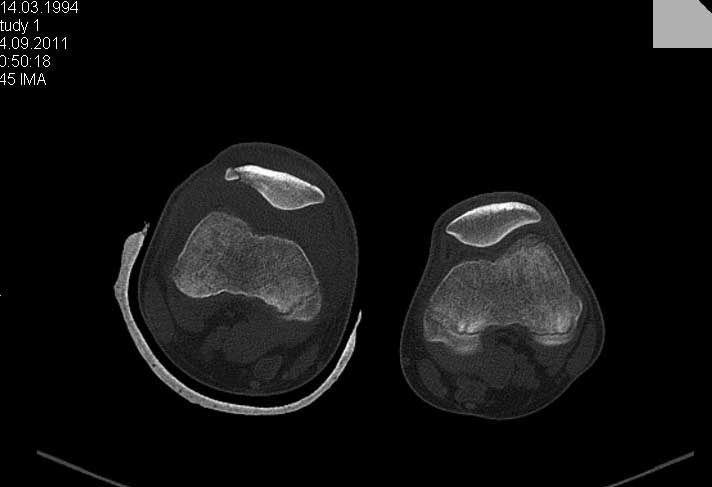

Обратился ребёнок 15 лет с оскольчатым переломом надколенника. Давность травмы 1 неделя.Поделитеся пожалуйста опытом.

Показанием к оперативному лечению перелома надколенника у подростков есть внутрисуставное смещение отломков больше 3 мм.